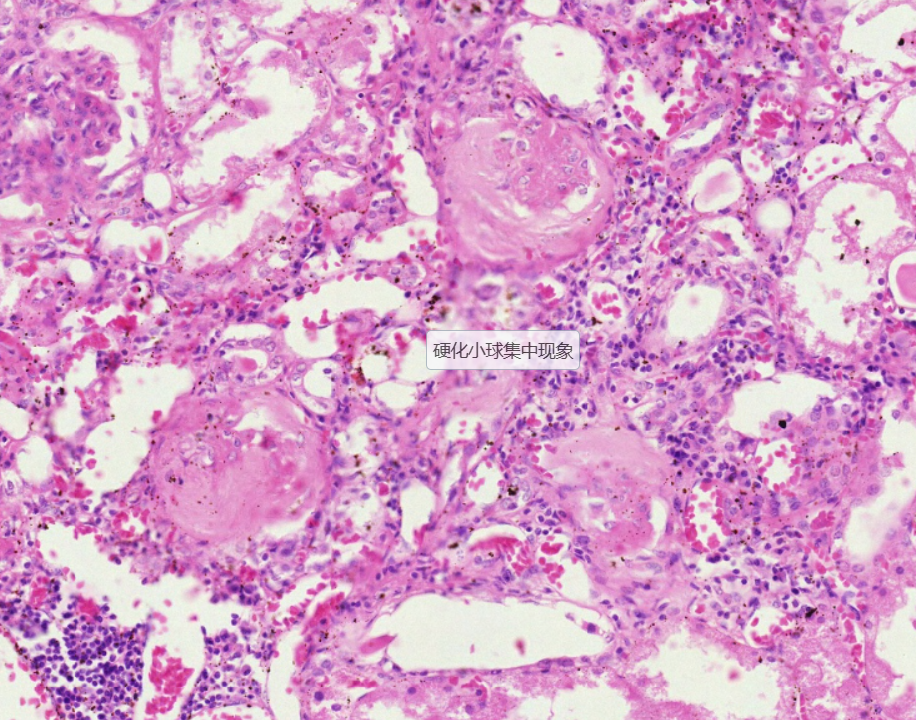

2 系膜增生性肾炎

2.肾小球系膜细胞重度增生

3.肾小球硬化

4.间质血管扩张充血